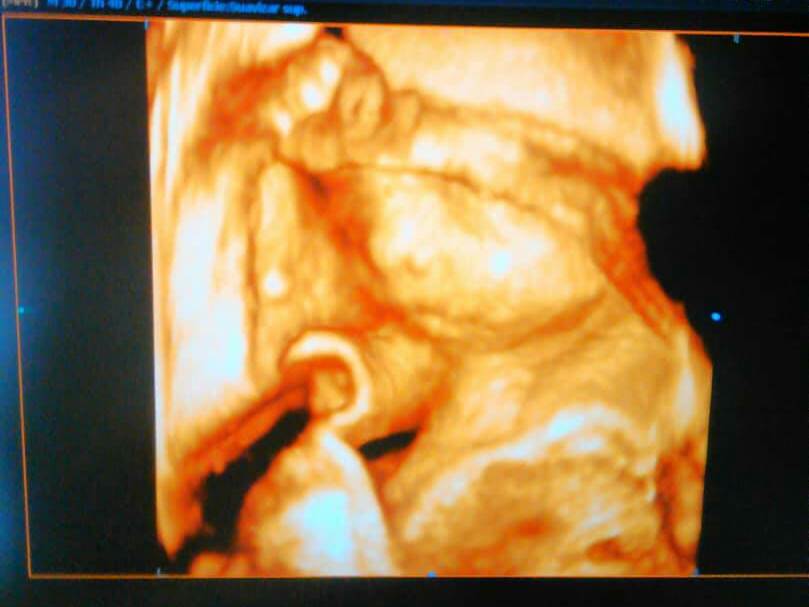

Hoy en día ya tengo 7 meses, me realice el eco morfológico, y gracias a DIOS mi princesa está totalmente sana, grande y gorda. Se mueve mucho y cómo van a poder apreciar en esta ecografía esta completica y formadita. Solo esperamos el día de su llegada con mucho anhelo y ansias.